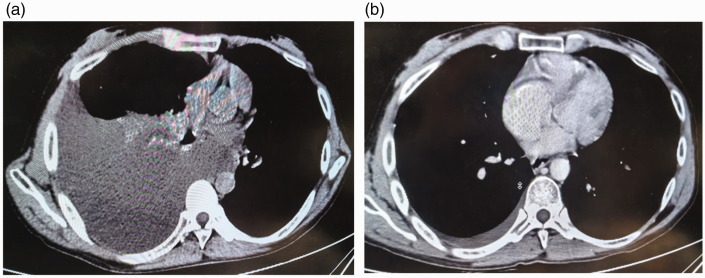

本病例报告详细介绍了肝硬化患者乳糜胸膜和腹膜积液的处理。患者有28年未经治疗的乙肝病史,到高海拔地区旅行后出现呼吸困难和咳嗽。影像学和实验室检查证实有乳糜积液。治疗包括胸腔穿刺、穿刺、抗生素、生长抑素类似物和支持性护理。患者病情明显好转,出院后随访无复发。本病例强调了肝硬化乳糜积液的早期诊断和保守治疗的重要性,强调了生长抑素类似物在减少积液形成和促进淋巴愈合方面的潜在作用。

This case report details the management of a patient with cirrhosis who developed chylous pleural and peritoneal effusions. The patient, with a 28-year history of untreated hepatitis B, presented with dyspnea and cough after traveling to a high-altitude area. Imaging and laboratory tests confirmed the presence of chylous effusions. Treatment included thoracentesis, paracentesis, antibiotics, somatostatin analogs, and supportive care. The patient showed significant improvement and was discharged with no recurrence at follow-up. This case highlights the importance of early diagnosis and conservative management of chylous effusions in cirrhosis, emphasizing the potential role of somatostatin analogs in reducing effusion formation and promoting lymphatic healing.